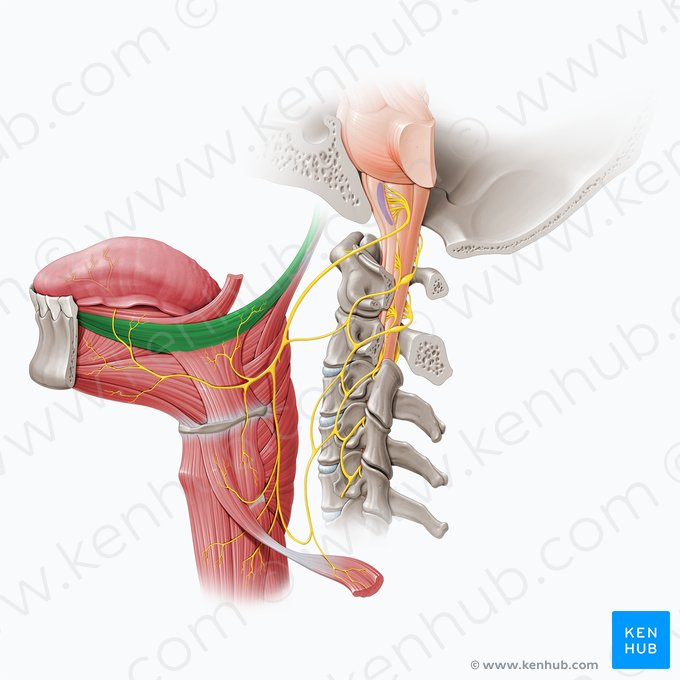

Oropharynx

green highlight

Laryngopharynx

blue highlight